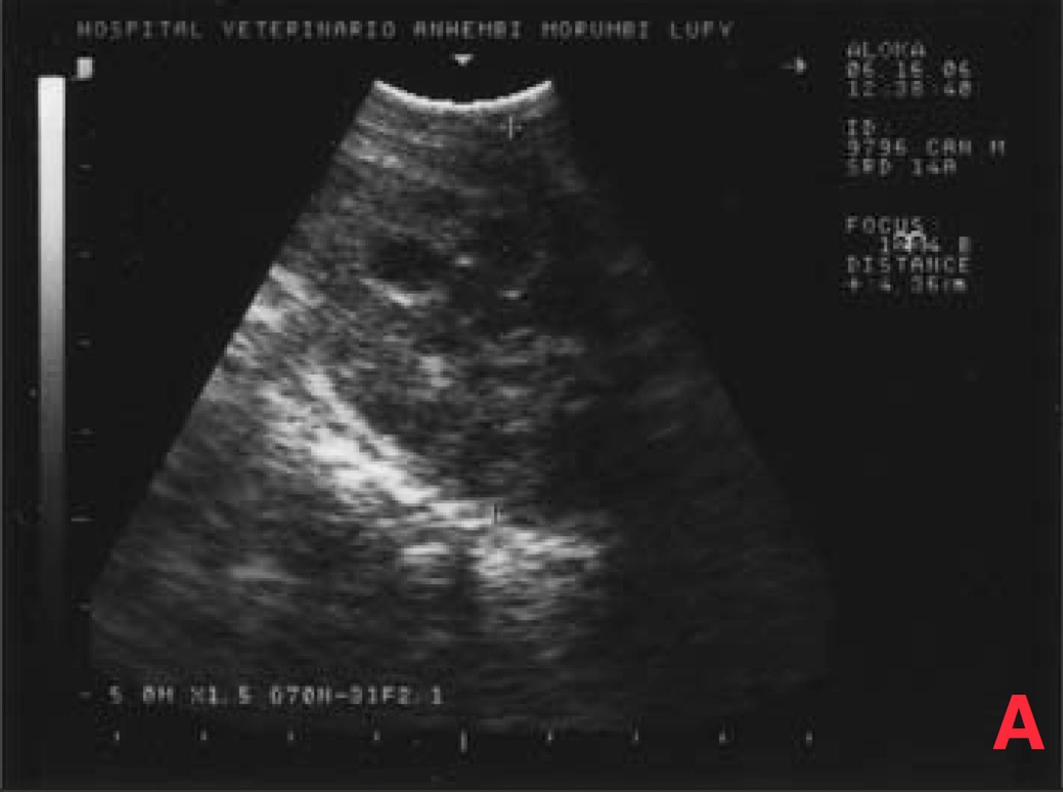

Não houve alterações na avaliação hematológica, na bioquímica (creatinina, ureia) e na radiografia torácica, porém o exame ultrassonográfico mostrou aumento de próstata (4,3 x 3,8 x 2,8cm), com áreas císticas difusas pelo parênquima (imagens sugestivas de hiperplasia prostática benigna/prostatite); somente um testículo em bolsa escrotal; grande aumento de volume em região inguinal esquerda (formação heterogênea em ecotextura e ecogenicidade) e aumento de cadeia de linfonodos sublombares e ilíacos (medindo até 2,4 x 1,6cm, com ecogenicidade e ecotextura heterogêneas) (Figura 3).